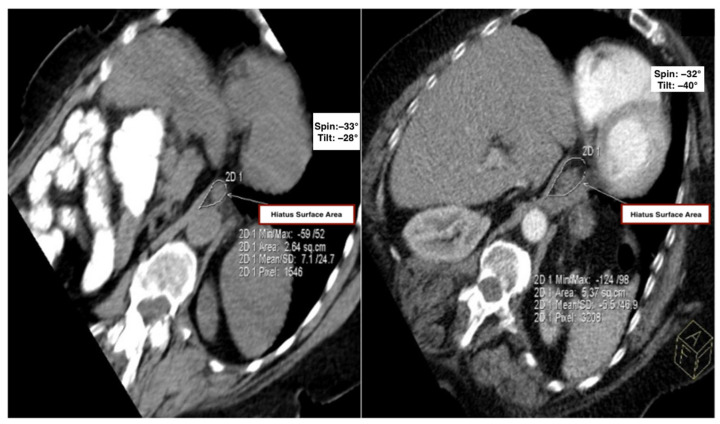

Methods: In this retrospective, single-center study, 100 adult patients (50 with thoracic kyphosis, defined as a Cobb angle of ≥50° and 50 age- and sex-matched controls) underwent multidetector CT (MDCT). Hiatal surface area (HSA) was measured on a standardized oblique axial plane aligned with the diaphragmatic crura. Correlation and multivariable regression analyses were performed to assess relationships between Cobb angle and HSA.

Results: The kyphosis group showed significantly larger HSA than controls (5.14 ± 1.31 cm2 vs. 3.59 ± 0.74 cm2; p < 0.001). A moderate positive correlation was found between Cobb angle and HSA (r = 0.336, p = 0.017). Multivariable analysis identified the Cobb angle as an independent predictor of HSA (β = 0.028; p = 0.017), while age and sex were not significant predictors. No overt herniation was present in any subject.